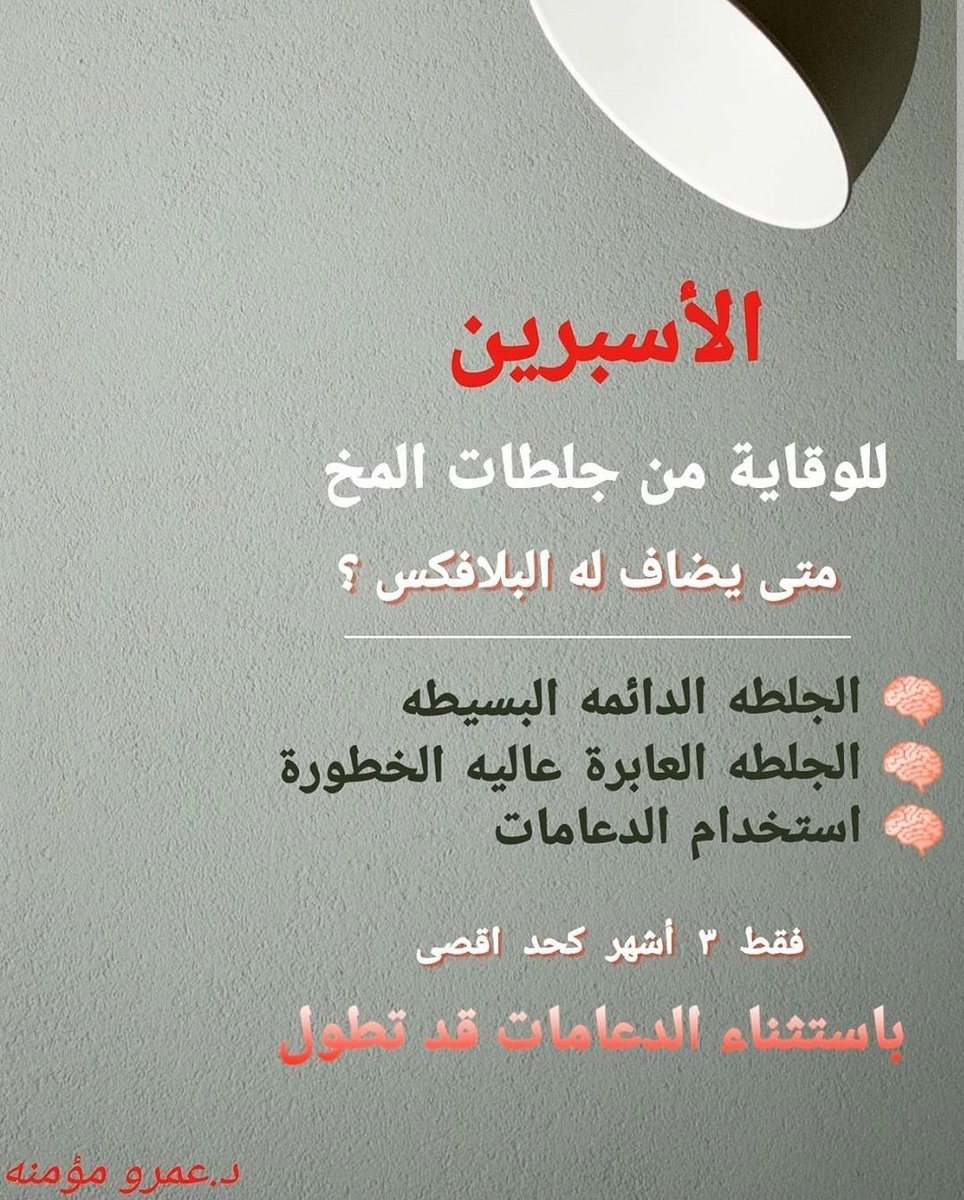

معلومات توعويه مفيدة عن #الاسبرين و #السكته_الدماغيه_الاقفاريه✌

💥بشكل عام

🧠الاصل علاج سيوله صحيح واحد يكفي إلا حالات نادرة قد نحتاج اكثر

♦️فلو استخدمت الاسبرين+البلافكس أو ادويه سيوله اخرى كالوارفارين تأكد من طبيبك المدة والسبب

💥بشكل عام

🧠الاصل علاج سيوله صحيح واحد يكفي إلا حالات نادرة قد نحتاج اكثر

♦️فلو استخدمت الاسبرين+البلافكس أو ادويه سيوله اخرى كالوارفارين تأكد من طبيبك المدة والسبب